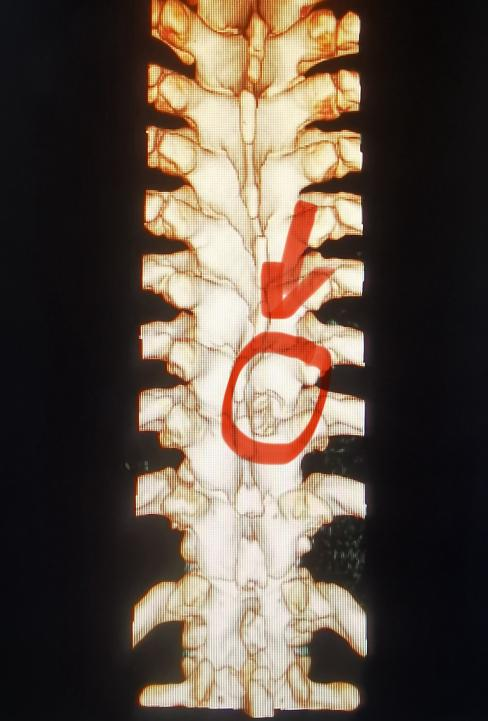

九江市第一人民医院疼痛科王晓英主任团队凭借丰富的临床专科经验,结合患者的病史、疼痛部位与性质、症状、体征,结合影像学检查精准锁定“真凶”——胸椎黄韧带骨化症。压迫脊神经根,导致相应部位疼痛及感觉异常。与董先生充分沟通后,王晓英主任团队为他实施脊柱内镜下胸椎椎管减压成形术+脊神经根粘连松解术。麻醉苏醒后的第一句话就是:“我不疼了”!董先生目前已平稳康复出院。

胸椎黄韧带骨化症(TOLF)是胸椎管内连接椎板的黄韧带发生异常骨化,这好比韧带逐渐变成了骨头,从而压迫脊髓或神经根,引发一系列症状。多发于50-70岁的中老年人、男性更为常见,亚洲人群发病率较高。常与退变、代谢异常(如糖尿病)等因素相关。